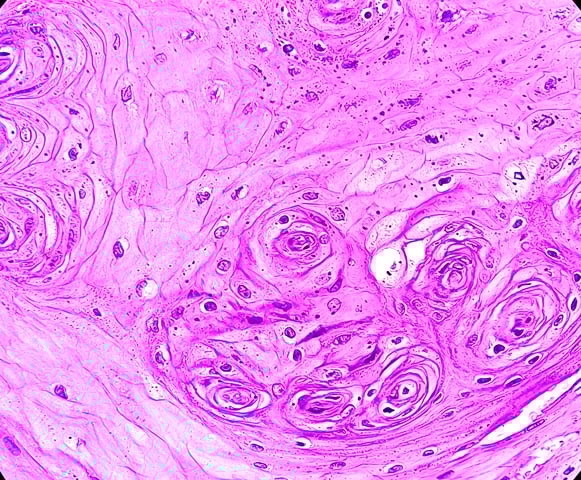

- Lichen planus: Chronic condition that causes an itchy, inflammatory rash in the mouth or on the skin.